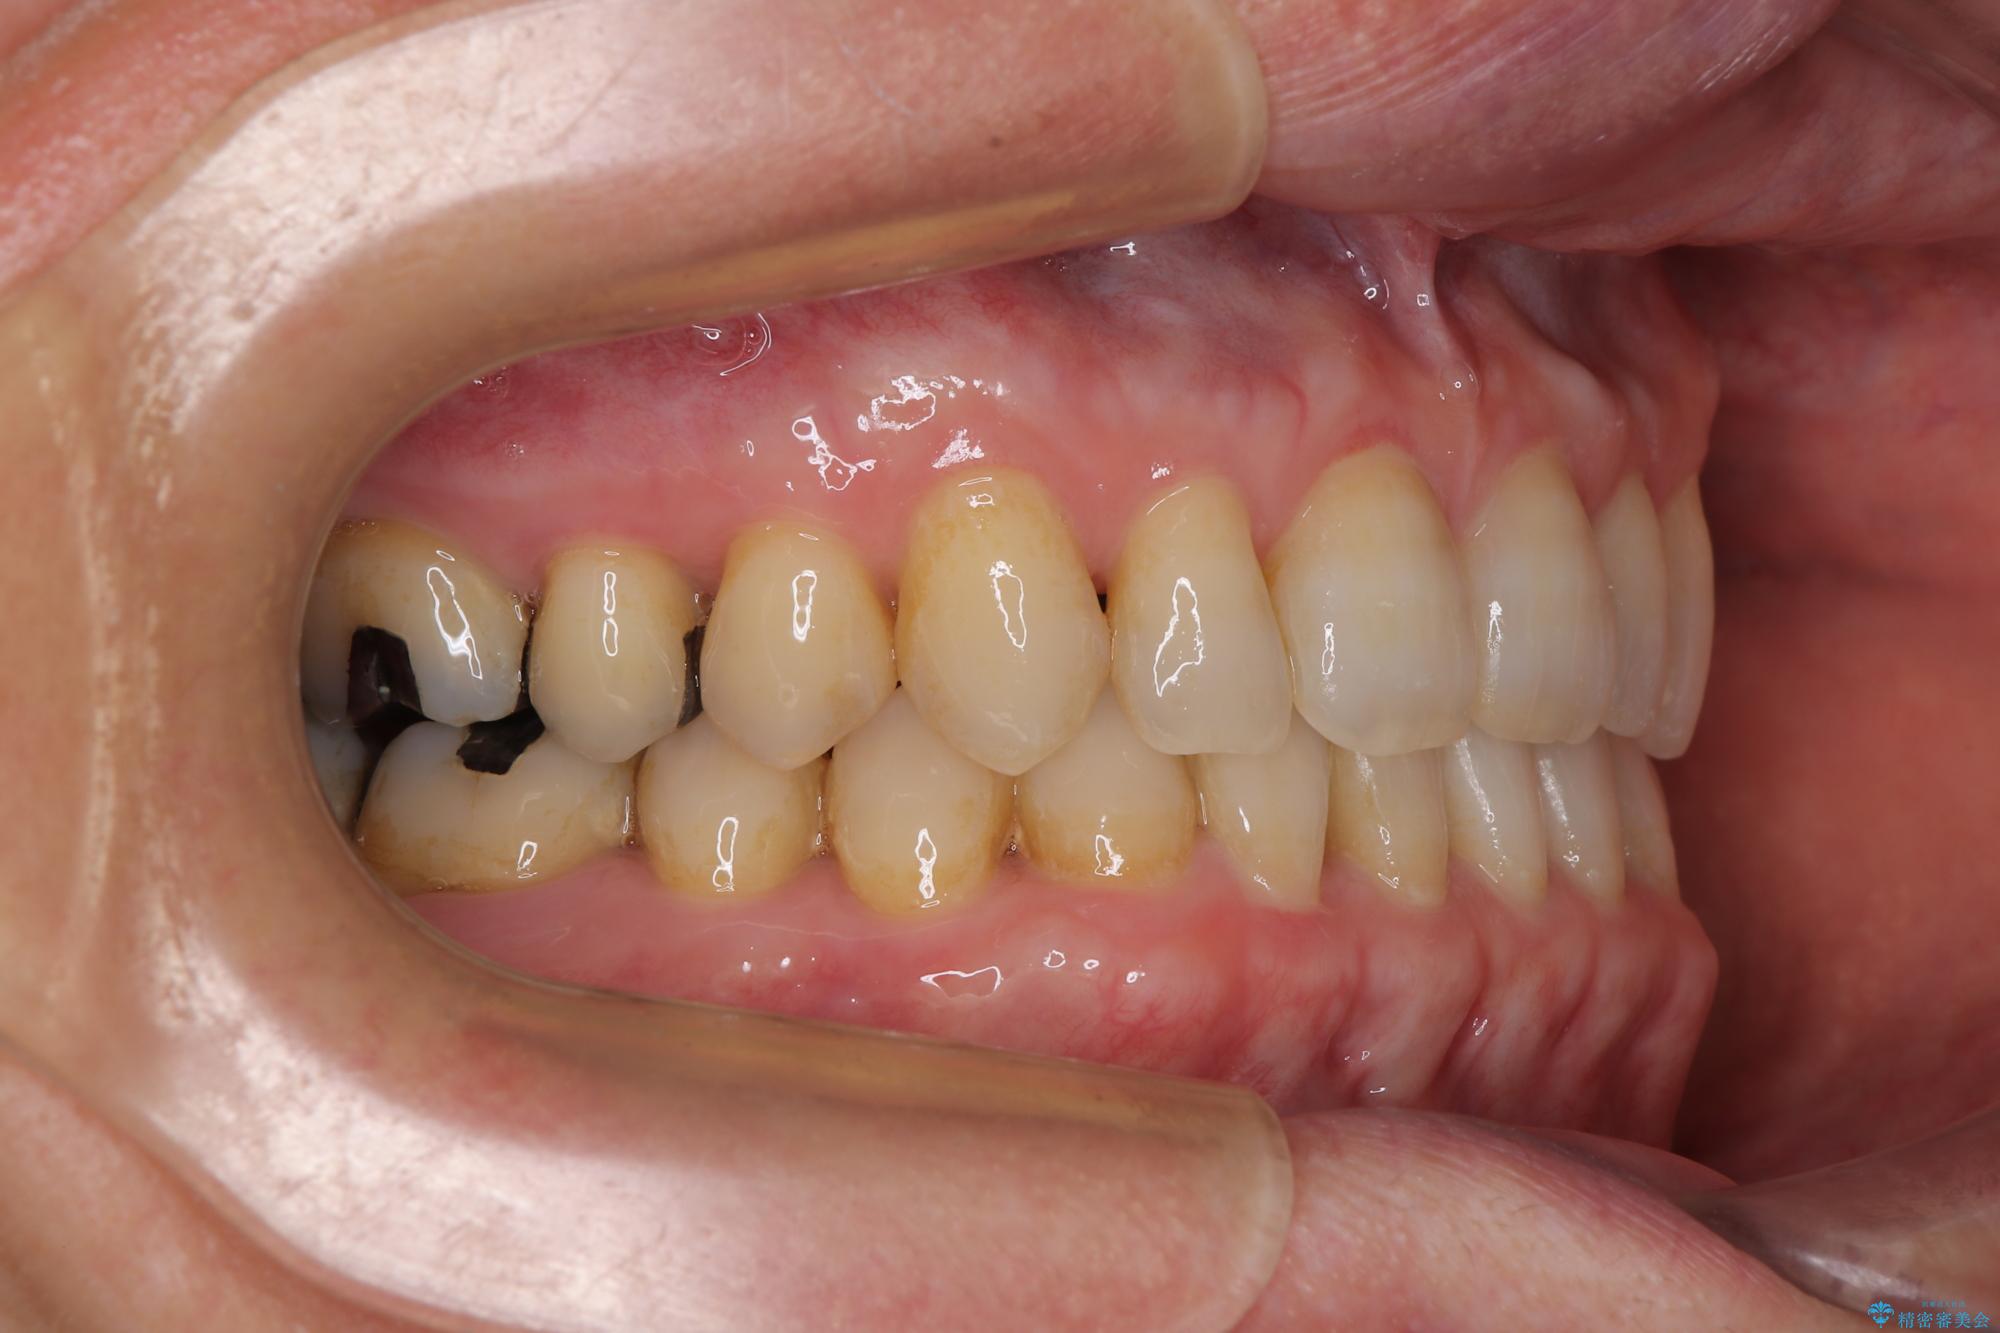

- 前歯のデコボコと隙間の空いた歯列を気にして来院された患者様です。

下顎前歯が隠れるほどのディープバイトにより、強い咬合力と突き上げで上顎歯列に隙間が空いている状態でした。

手前に傾斜している奥歯をワイヤー装置で立ち上がらせ、咬み合わせの高さを挙上することで突き上げを解消し、空隙歯列を改善していくこととしました。